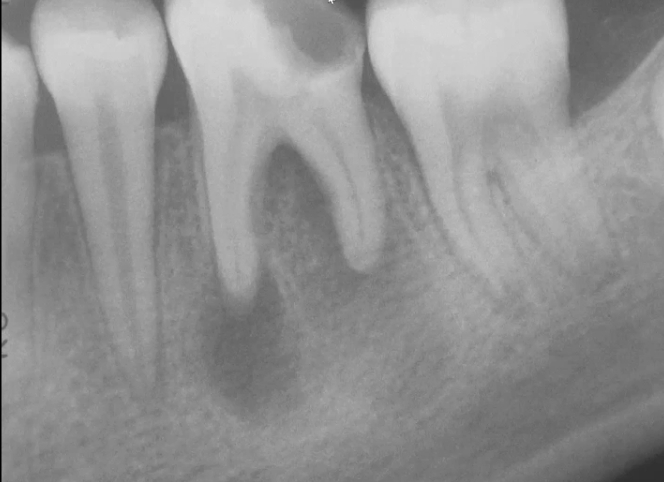

Q

A

periapical radiolucency

- tooth also has a carious lesion

What can a periapical radiolucency be?

• periapical abscess

• periapical granuloma

• periapical cyst